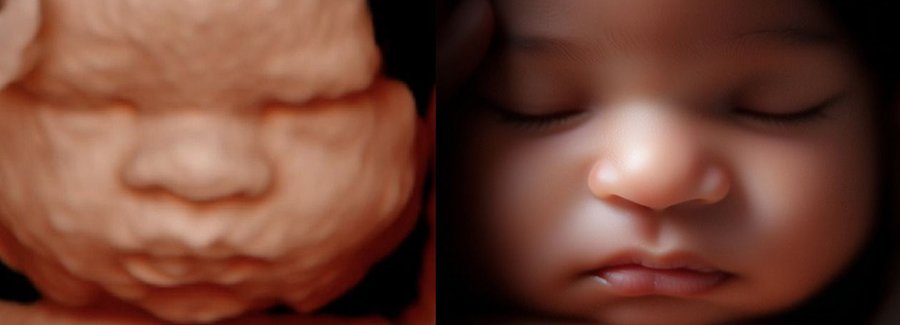

Often referred to as 5D, HD or FRV (fetal realistic view), 5D/HD is the newest development in pregnancy imaging. It captures and combines high definition volume data to create automated images with amazing color and clarity so you can see your baby as though you were looking from inside the womb.